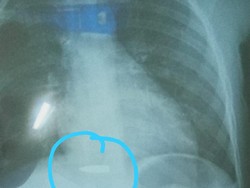

Proyektil peluru yang bersarang di tubuh MA (10), bocah asal Kampung Babakan Cianjur, Cihampelas, Kabupaten Bandung Barat (KBB), berhasil dikeluarkan.